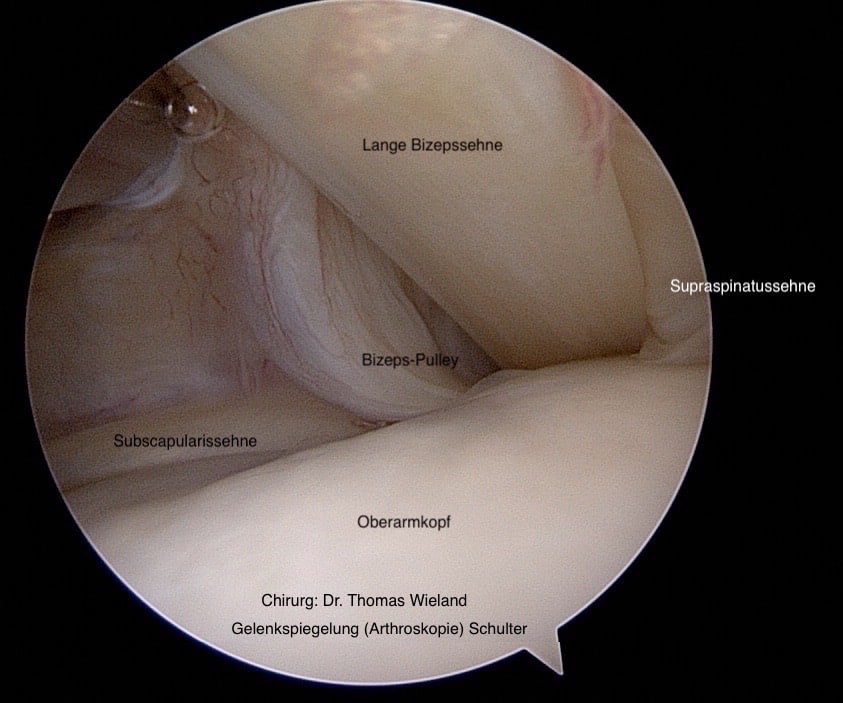

Die Rotatorenmanschette besteht aus 4 Muskeln mit ihren Sehnen, der Supraspinatus-, der Infraspinatus-, der Subscapularis– und der Teres minor Muskel. Dieser Muskel-Sehnenmantel legt sich wie eine Kapuze über den Oberarmkopf und kontrolliert so jede Drehung des Armes von der Schulter aus. Zusätzlich ist eine intakte Rotatorenmanschette für die Stabilität des Schultergelenkes sehr wichtig. Verletzungen an der Rotatorenmanschette (meist die Supraspinatussehne) sind sehr häufig, da die Rotatorenmanschette in der Schulter großen Belastungen unterliegt.

Verletzungsmuster an der Rotatorenmanschette (Supraspinatussehne, Infraspinatussehne, Subscapularissehne)